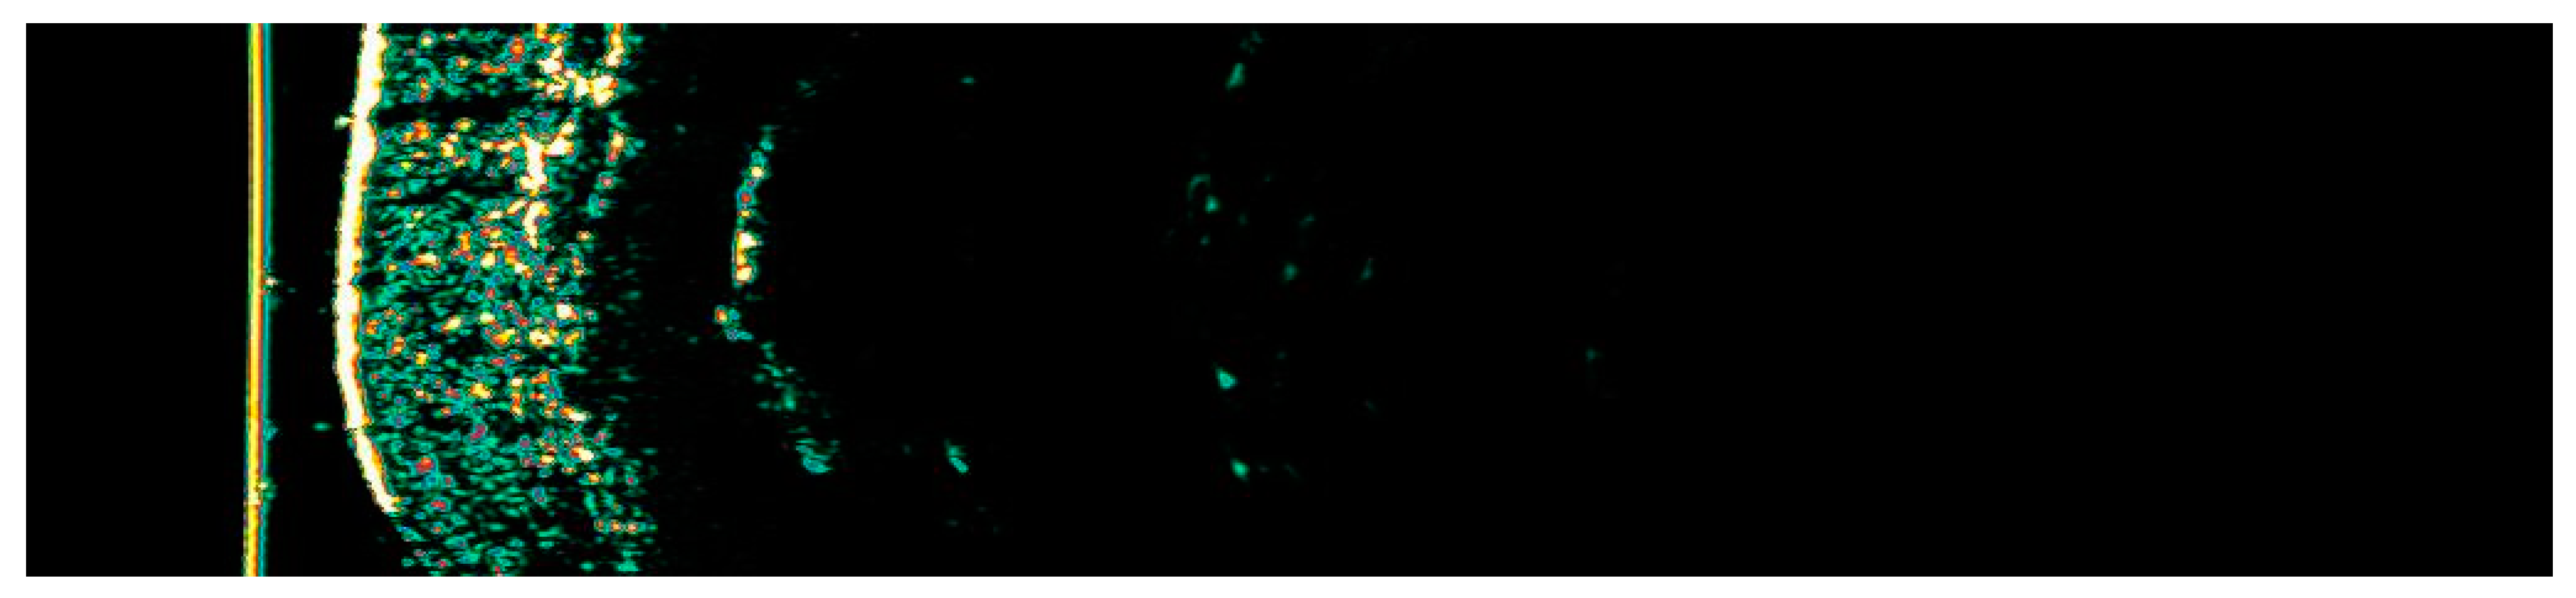

Figure 7. Ultrasonographic image of BCC on the nose.

The Figure 1, Figure 2, Figure 3, Figure 4, Figure 5, Figure 6, Figure 7, Figure 8, Figure 9, Figure 10, Figure 11, Figure 12, Figure 13, Figure 14, Figure 15, Figure 16, Figure 17, Figure 18, Figure 19, Figure 20, Figure 21, Figure 22, Figure 23, Figure 24, Figure 25, Figure 26, Figure 27 and Figure 28 alternately display ultrasound images and dermoscopic observations of the treated basal cell carcinoma (BCC) lesions. These images provide a visual representation of the textural and vascular changes observed during different stages of the healing process post-HIFU treatment, demonstrating the involution from immediate tissue responses to the long-term healing and remodeling of the skin.